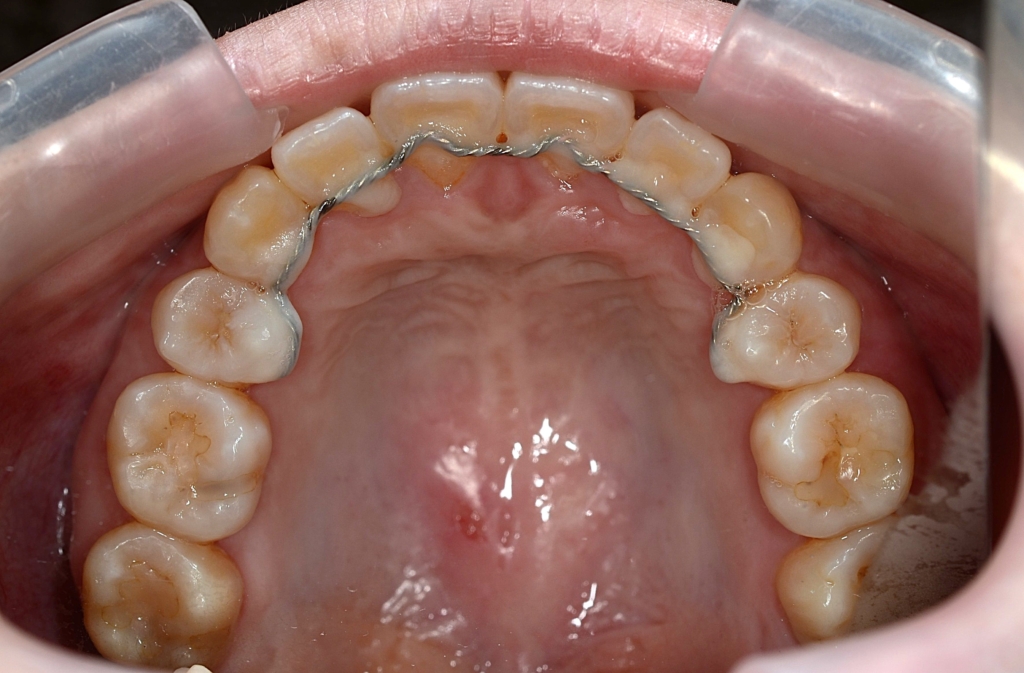

【保定】 上下ともフィックスタイプ&クリアリテーナー

ついでに、歯並びの比較です

上段が矯正治療前、下段が矯正治療後